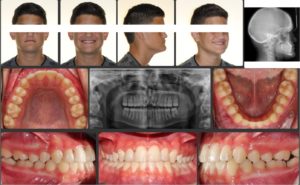

A 12.4 year old caucasian male presents with a chief complaint of “underbite and crooked teeth”